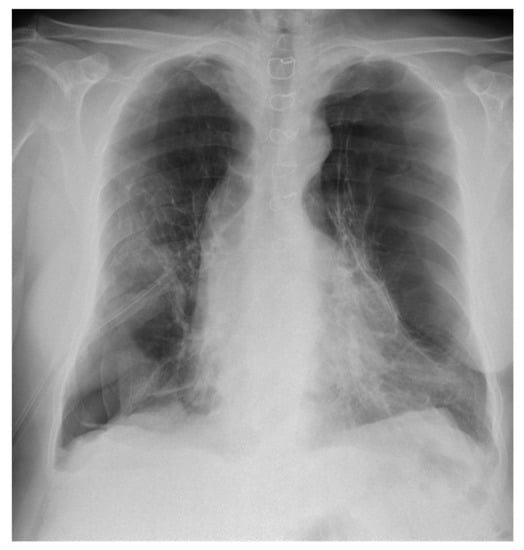

2.3. Diagnostic Assessment and Therapeutic Intervention

2.4. Final Diagnosis